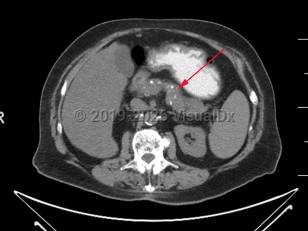

The diagnosis of chronic pancreatitis can be challenging and relies on a combination of symptomatology, histologic, radiographic, and endoscopic findings. There is no single gold standard test to confirm the diagnosis. Some patients present with recurrent episodes of epigastric abdominal pain and pancreatic enzyme elevation, while others can present with asymptomatic diabetes mellitus and be found to have chronic pancreatitis. Regardless of the predisposing medical condition precipitating the development of chronic pancreatitis, radiographically, pancreatic atrophy and calcification with a dilated pancreatic duct are often but not always seen. Histologically, pancreatic fibrosis, duct distortion, and intra-ductal calcification are often but not always appreciated.